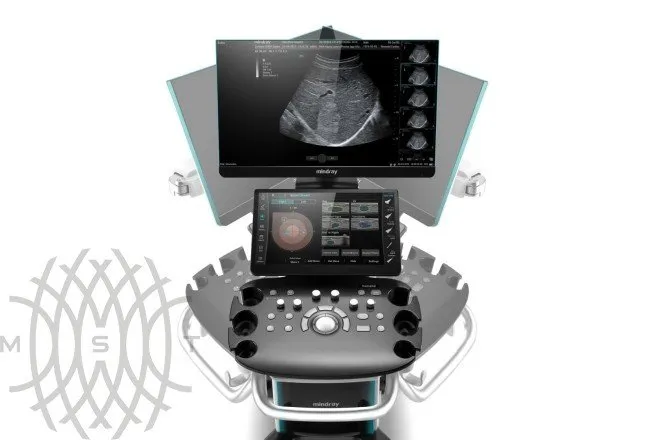

УЗИ аппарат Mindray Consona N9

Mindray Consona N9 — это консольная ультразвуковая система премиального уровня, разработанная компанией Миндрей для комплексной диагностики. Аппарат построен на платформе ZST+ (Zone Sonography® Technology+), которая обеспечивает высокую чёткость и однородность изображения даже при сложных клинических исследованиях. Благодаря широким возможностям визуализации, Consona N9 Миндрей успешно применяется в акушерстве, гинекологии, кардиологии, абдоминальной и общей диагностике. Система относится к классу «система ультразвуковой визуализации универсальная серии Consona», что подтверждает её универсальность и высокую клиническую ценность.

Эргономичный дизайн обеспечивает удобство использования: 23,8″ LED-монитор, 15,6″ сенсорная панель с управлением жестами, мобильная консоль с регулировкой по высоте и встроенный аккумулятор для автономной работы до 90 минут. Всё это делает аппарат удобным в ежедневной практике. Заказать и купить УЗИ аппарат Consona N9 можно у официальных дистрибьюторов, что гарантирует оригинальное оборудование, сервисное сопровождение и выгодные условия поставки. Таким образом, УЗИ аппарат Mindray Consona N9 Миндрэй — это выбор для клиник, которые ценят точность, инновации и надёжность.